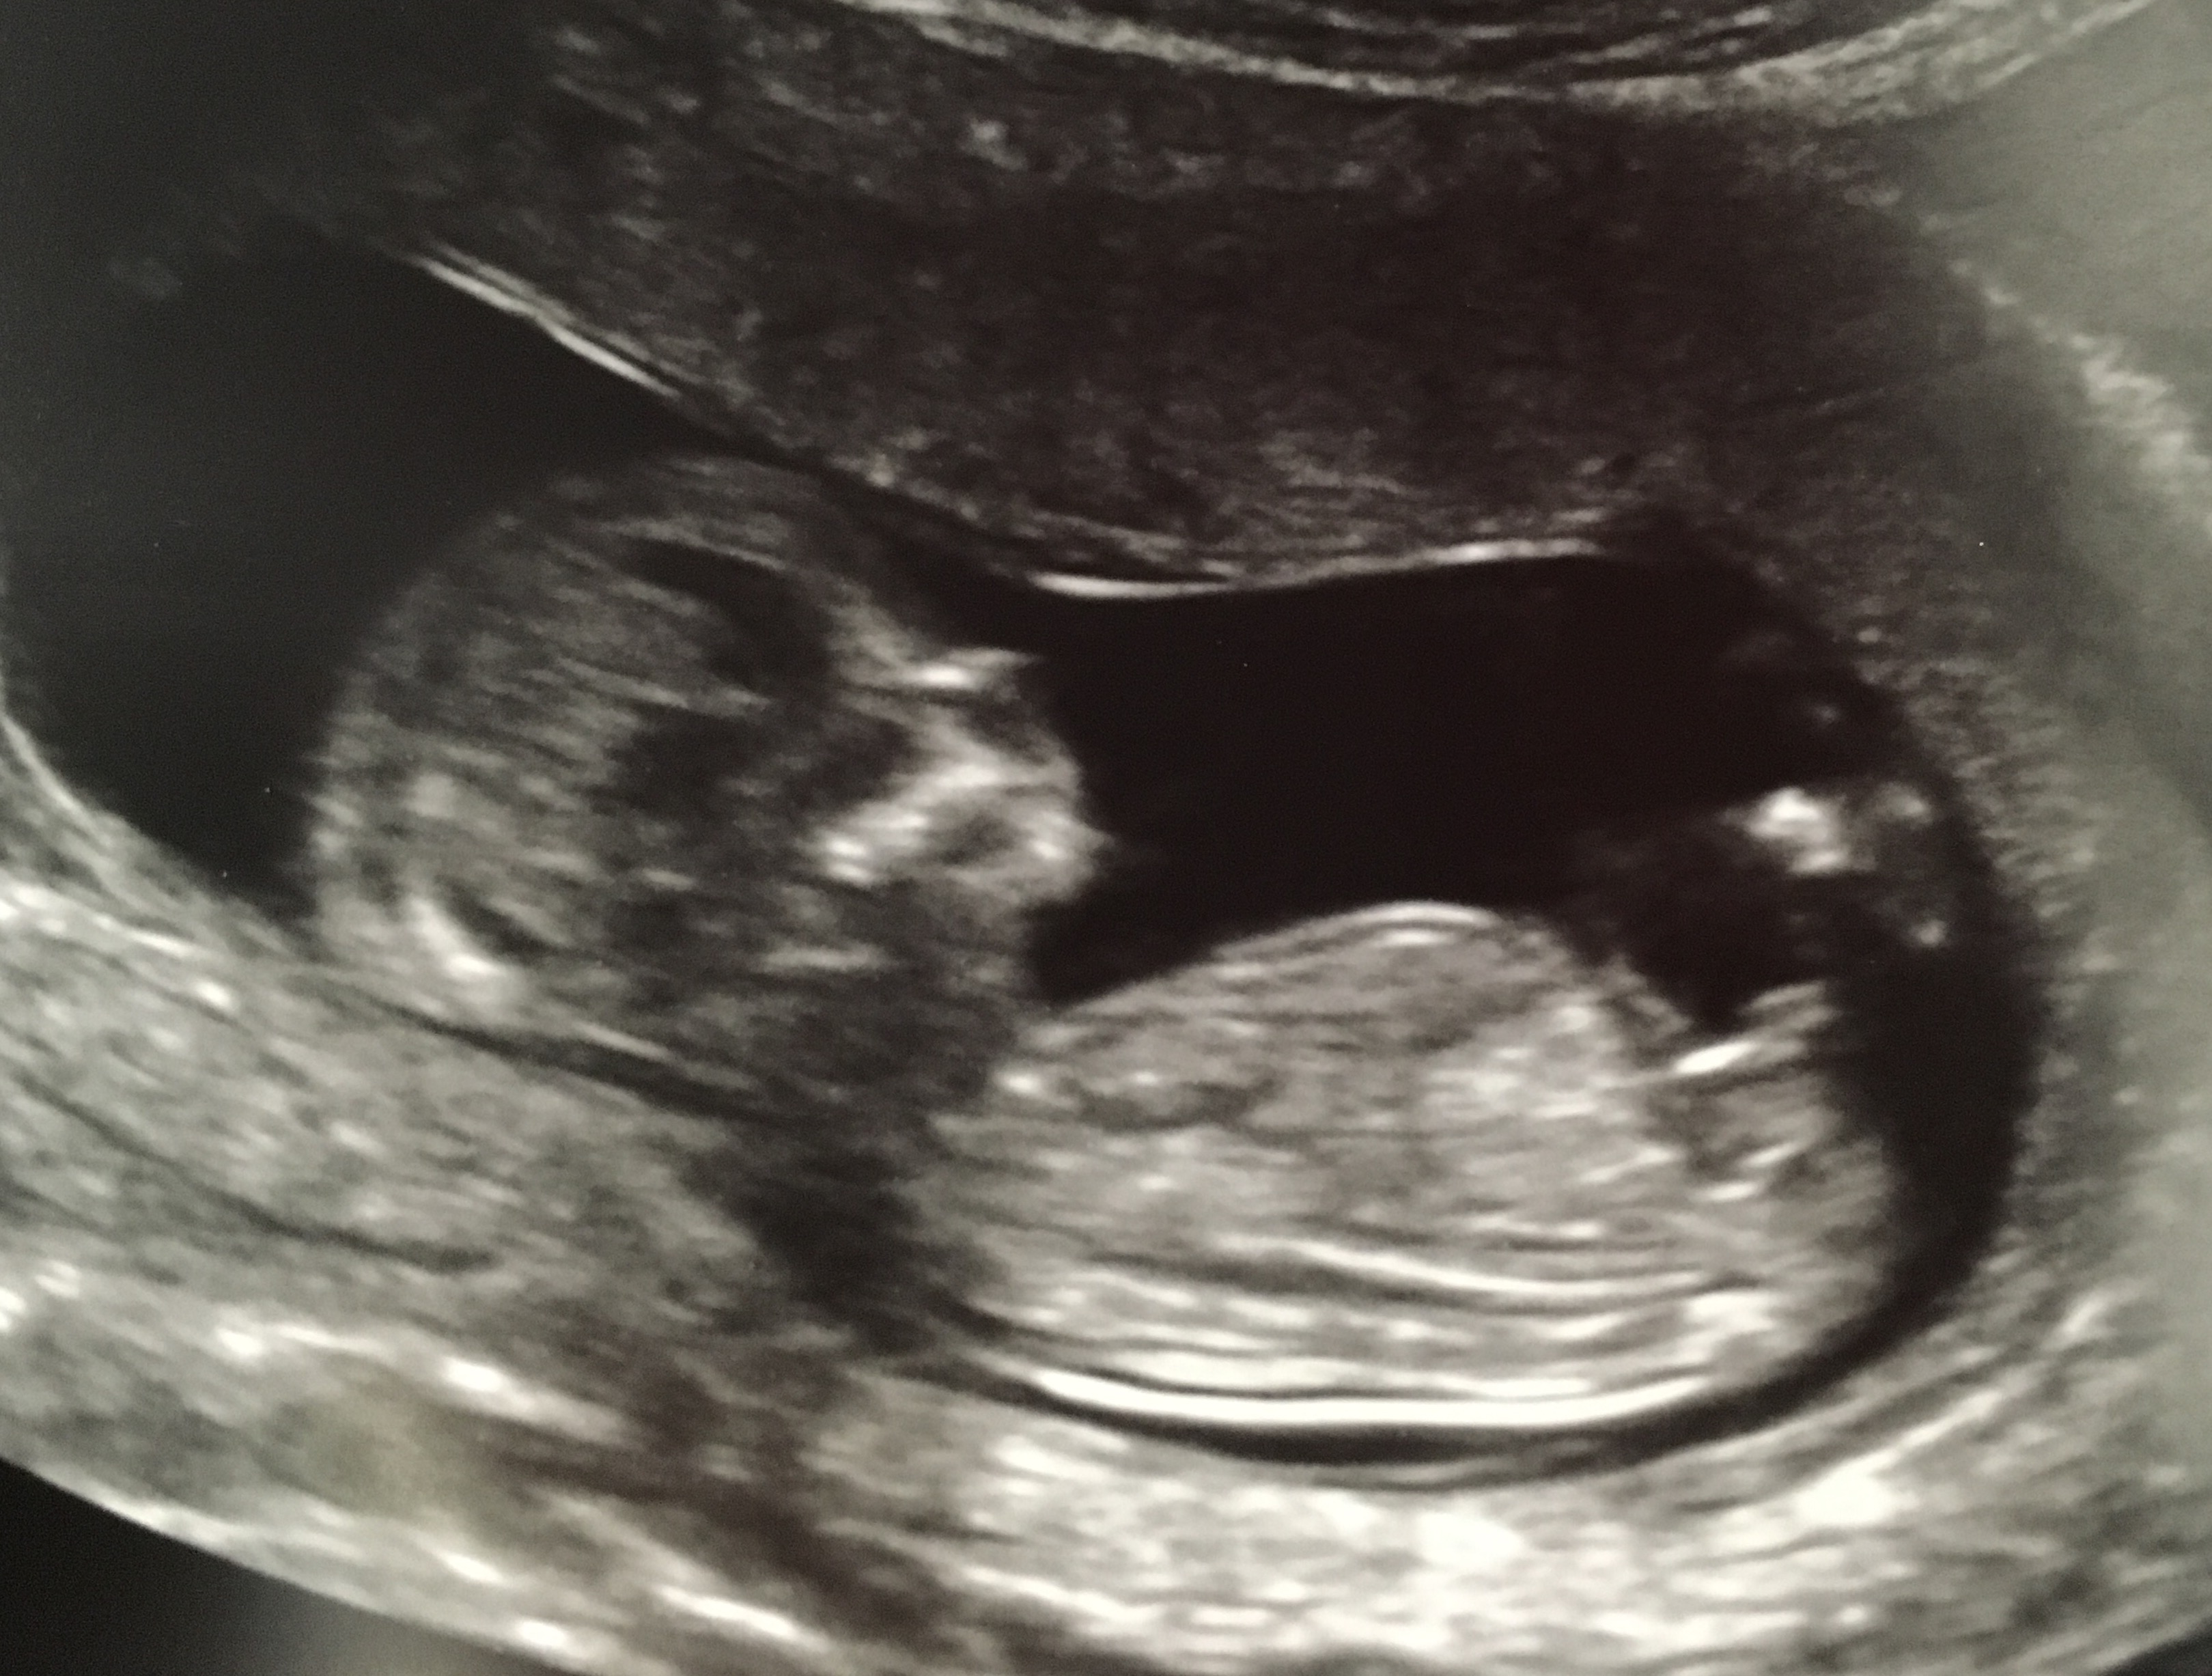

• So, my little cupcake looks like an absolute alien. The tech said that the part that looks like alien eyes is not the face. She said the part at the opposite end is the back of the head. Anybody know exactly what Im looking at here? This is a 12 almost 13 week scan.